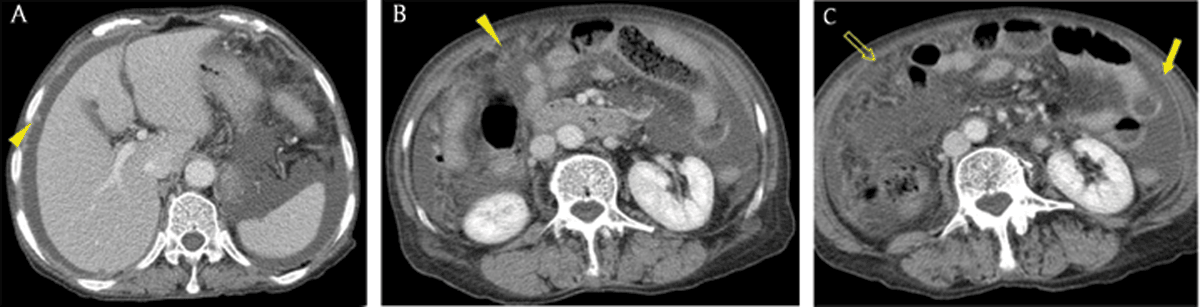

Figure 9

A 74-year-old woman with tuberculous peritonitis. Axial portal venous phase CT images showed multiple nodules (arrowheads), diffuse peritoneal thickening (arrow), ascites, and omental haziness (open arrow), findings that mimicked peritoneal carcinomatosis.